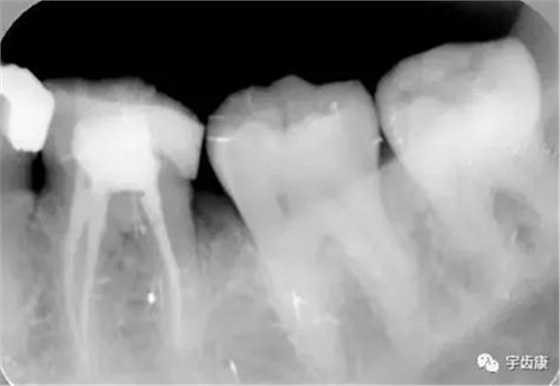

X線閱片知識(shí)